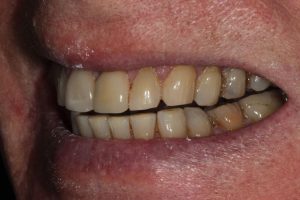

Full Mouth Rehabilitation

Full mouth Treatment – missing upper front teeth and mispositioned implants in the Lower left side meant planning was key here to get the desired result. Implants were placed to replace the missing teeth, veneers/crowns on the remaining upper teeth allowing an improvement in overall shape and colour, and the implant crowns on the lower left were change to bring into the line of the bite.